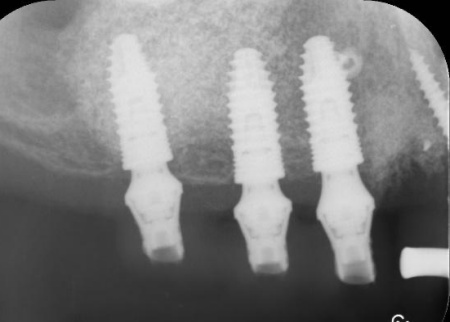

次に、右上奥歯と前歯にインプラント治療を行いました。

右上奥歯は、歯周病でインプラントを埋入するために必要な骨が不足していたため、上顎の奥にある上顎洞の底を押し上げて人工の骨を補う「サイナスリフト」という骨造成を併用しています。

右上前歯も同様に骨が少なかったため、こちらは骨の移植を行って骨量を確保したのち、インプラントを埋入しました。

インプラントが骨にしっかりとなじんだことを確認したら、白くて強度の高い人工歯「ジルコニアクラウン」を装着しました。